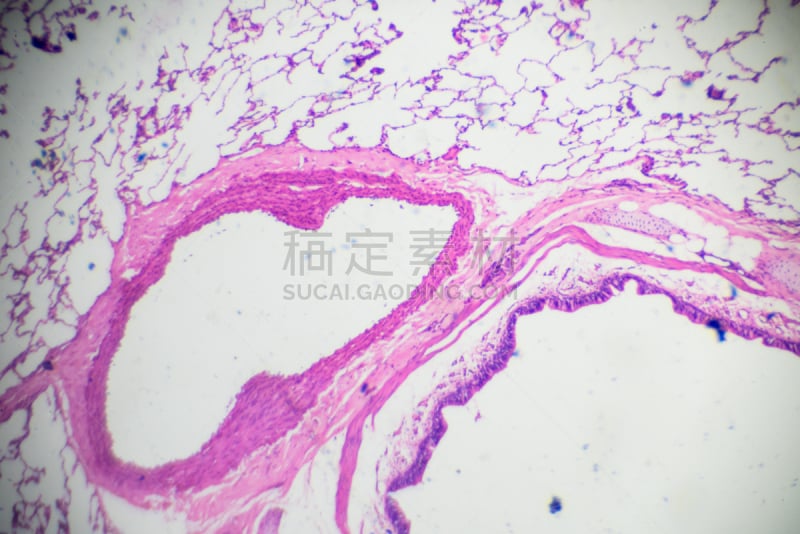

蓝色鳞状细胞详情